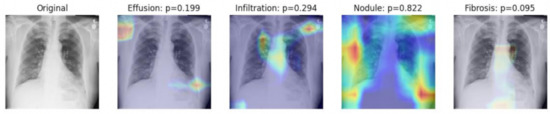

- We trained, validated, and tested the model using pretrained networks and compared the performance of each model using the ROC curves. We visualized the classification decision using Grad-CAM.

2.3. Visualization Using Class Activation Maps

3.4. Visualization